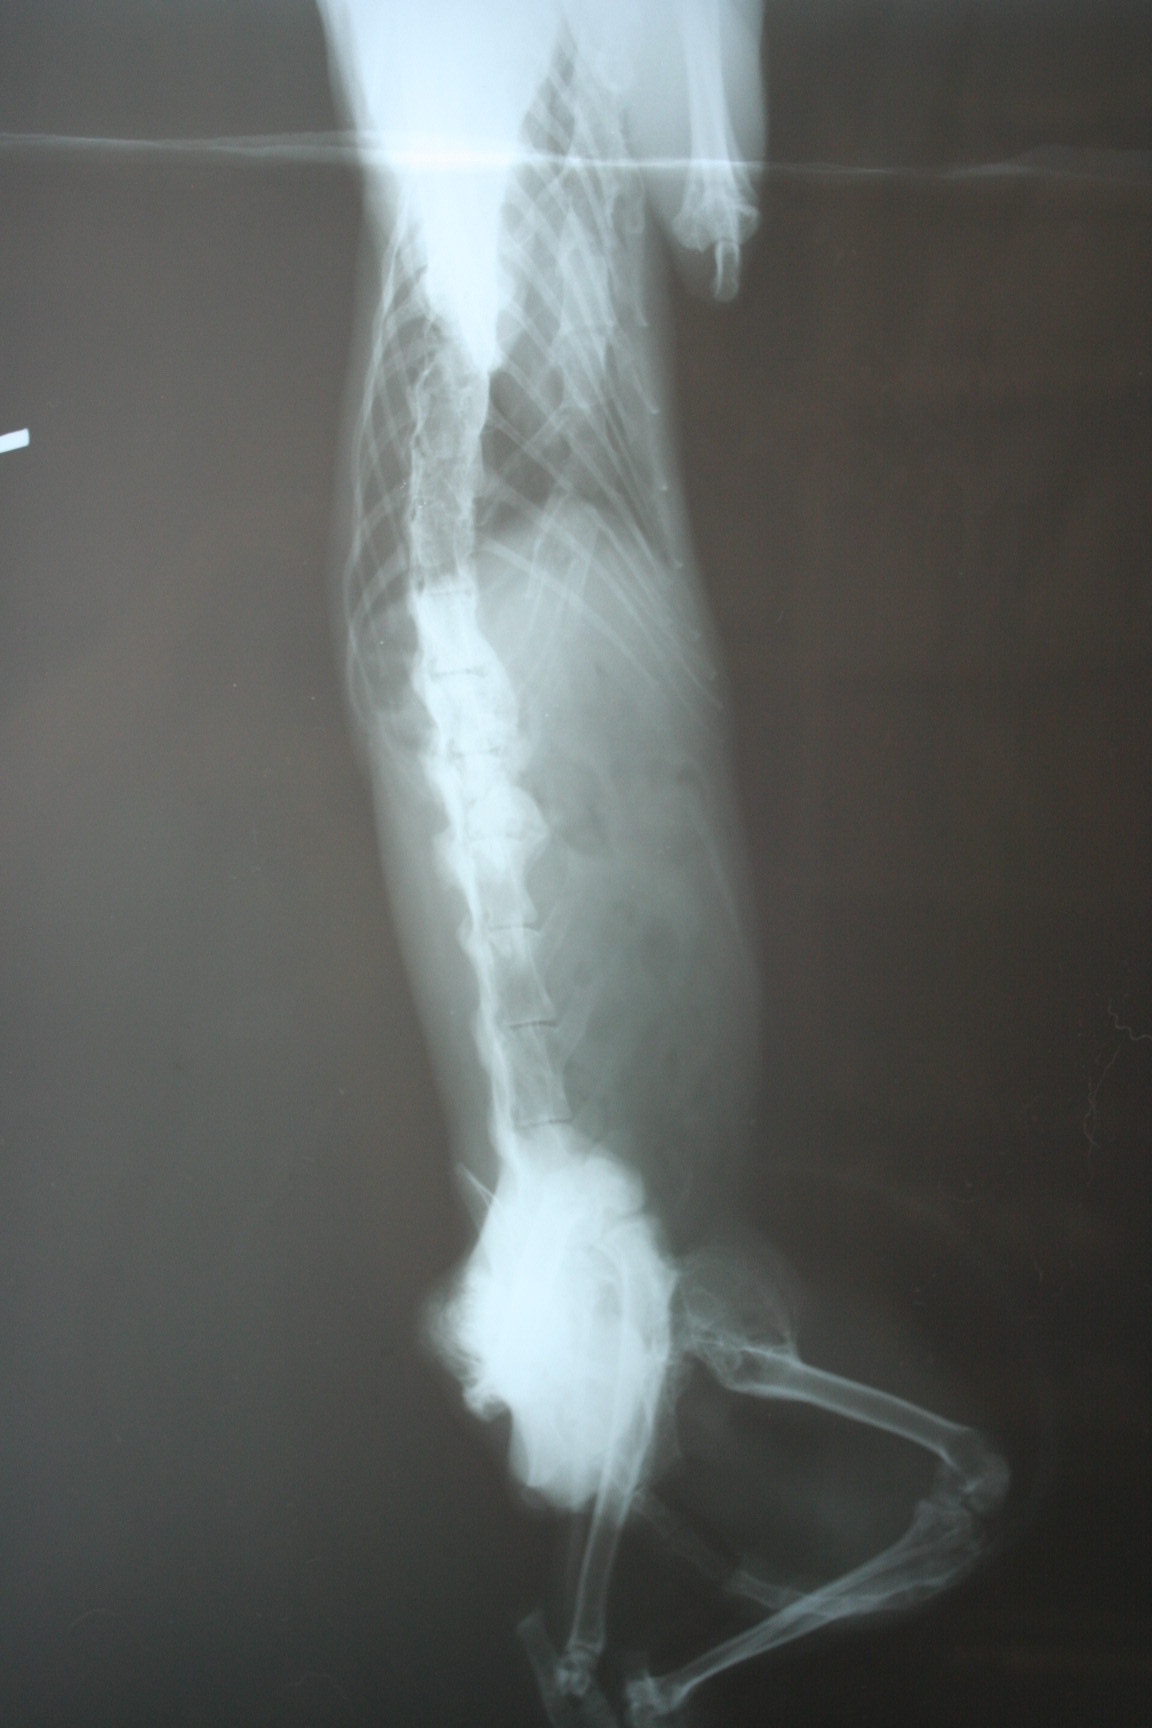

主題: .疑是車禍受傷沒有醫療倒至渾身僵硬.不能行動的貓咪 申請者姓名: 李惠卿 花色: 申請日期: 2013-04-12 17:20:11 申請者部落格: 申請者臉書網址: 所在縣市/合作醫院: 高雄市/回生動物醫院 治療費用: 6200元 需求人數: 7人 已結案 (2013-06-27 14:31:08) 報名人員: 家有三色喵(已付款)、詩詩(已付款)、Pei Shan Lee(已付款)、啾墨韶(已付款)、chiawei x2(已付款)、戀糖bear(已付款)、 候補人員: 動物病情說明: 學生坡網求救的貓咪.一到現場發現貓咪情況非常糟.骨瘦如材.直接就用抱的帶到醫院.貓咪骨頭懷疑是曾經車禍或外力受傷.沒有治療.骨頭不正常的增生.導致渾身僵硬.連頭都無法轉動..貓咪送醫時只能採取保守支持性的治療.灌食營養品..住院十天 後由通報的學生們接回照顧..醫療費用需要大家的幫忙.4000(4/2-4/11 400*10 住院費)+4/2洗澡剪毛600+4/2.4/3 X光片 (400*4)1600=6200